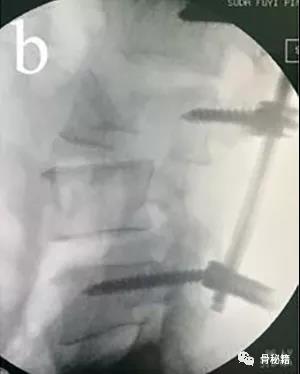

如果仅存在单纯的前后移位,后方没有绞索,也可应用以下方法

1、远端植入椎弓根螺钉,保留一些距离2、近端植入到底的椎弓根螺钉

3、若存在左右侧的位移,可让螺钉的开口侧面向近端脱位的一侧4、将棒塑性有一些弧度,先锁定远端后,利用棒的弹性来逐渐锁定近端达到复位

5、然后再将远端的钉子与棒逐个分离后拧入适当的深度,最后更换更合适的棒进行锁定